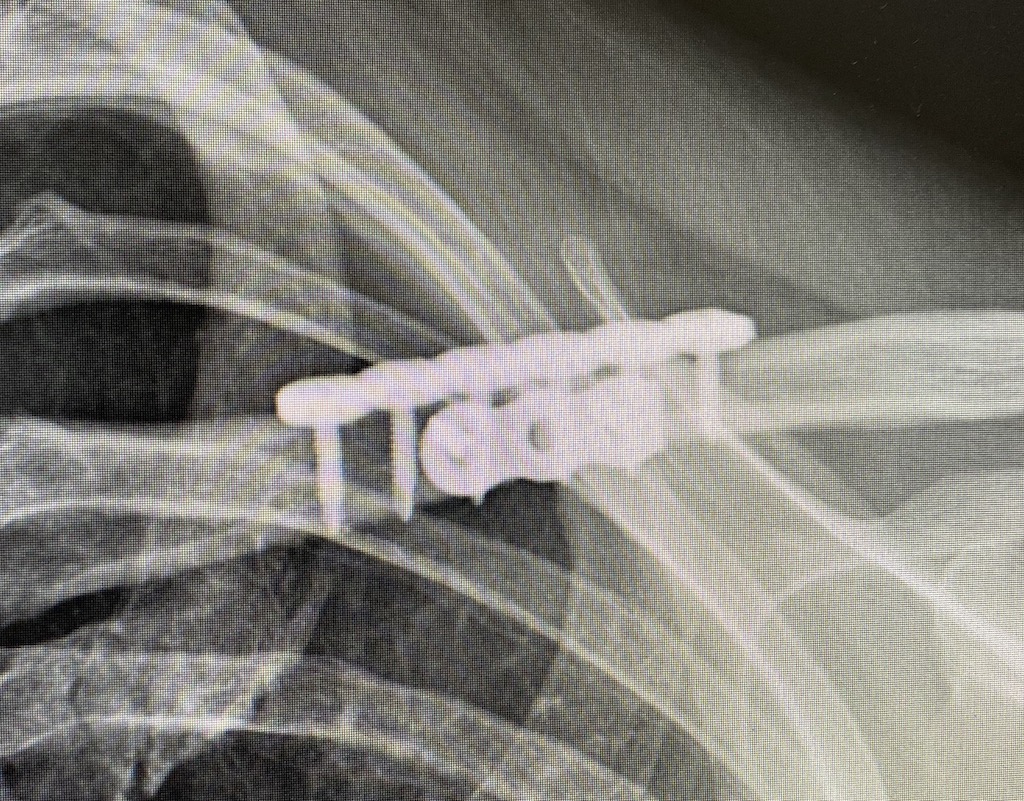

Plastic Surgery Case Study Clavicle Reduction Osteotomies (Shoulder Narrowing Surgery) in the What Is Shoulder Reduction Surgery This article reviews the most common. There are many ways you can injure your shoulders, including fracture, sprain and dislocation. Surgical techniques can range from minimally invasive arthroscopic procedures to more traditional open surgeries. This surgery is called shoulder arthroplasty. Shoulder replacement removes damaged areas of bone and replaces them with parts made of metal and plastic (implants). A shoulder. What Is Shoulder Reduction Surgery.